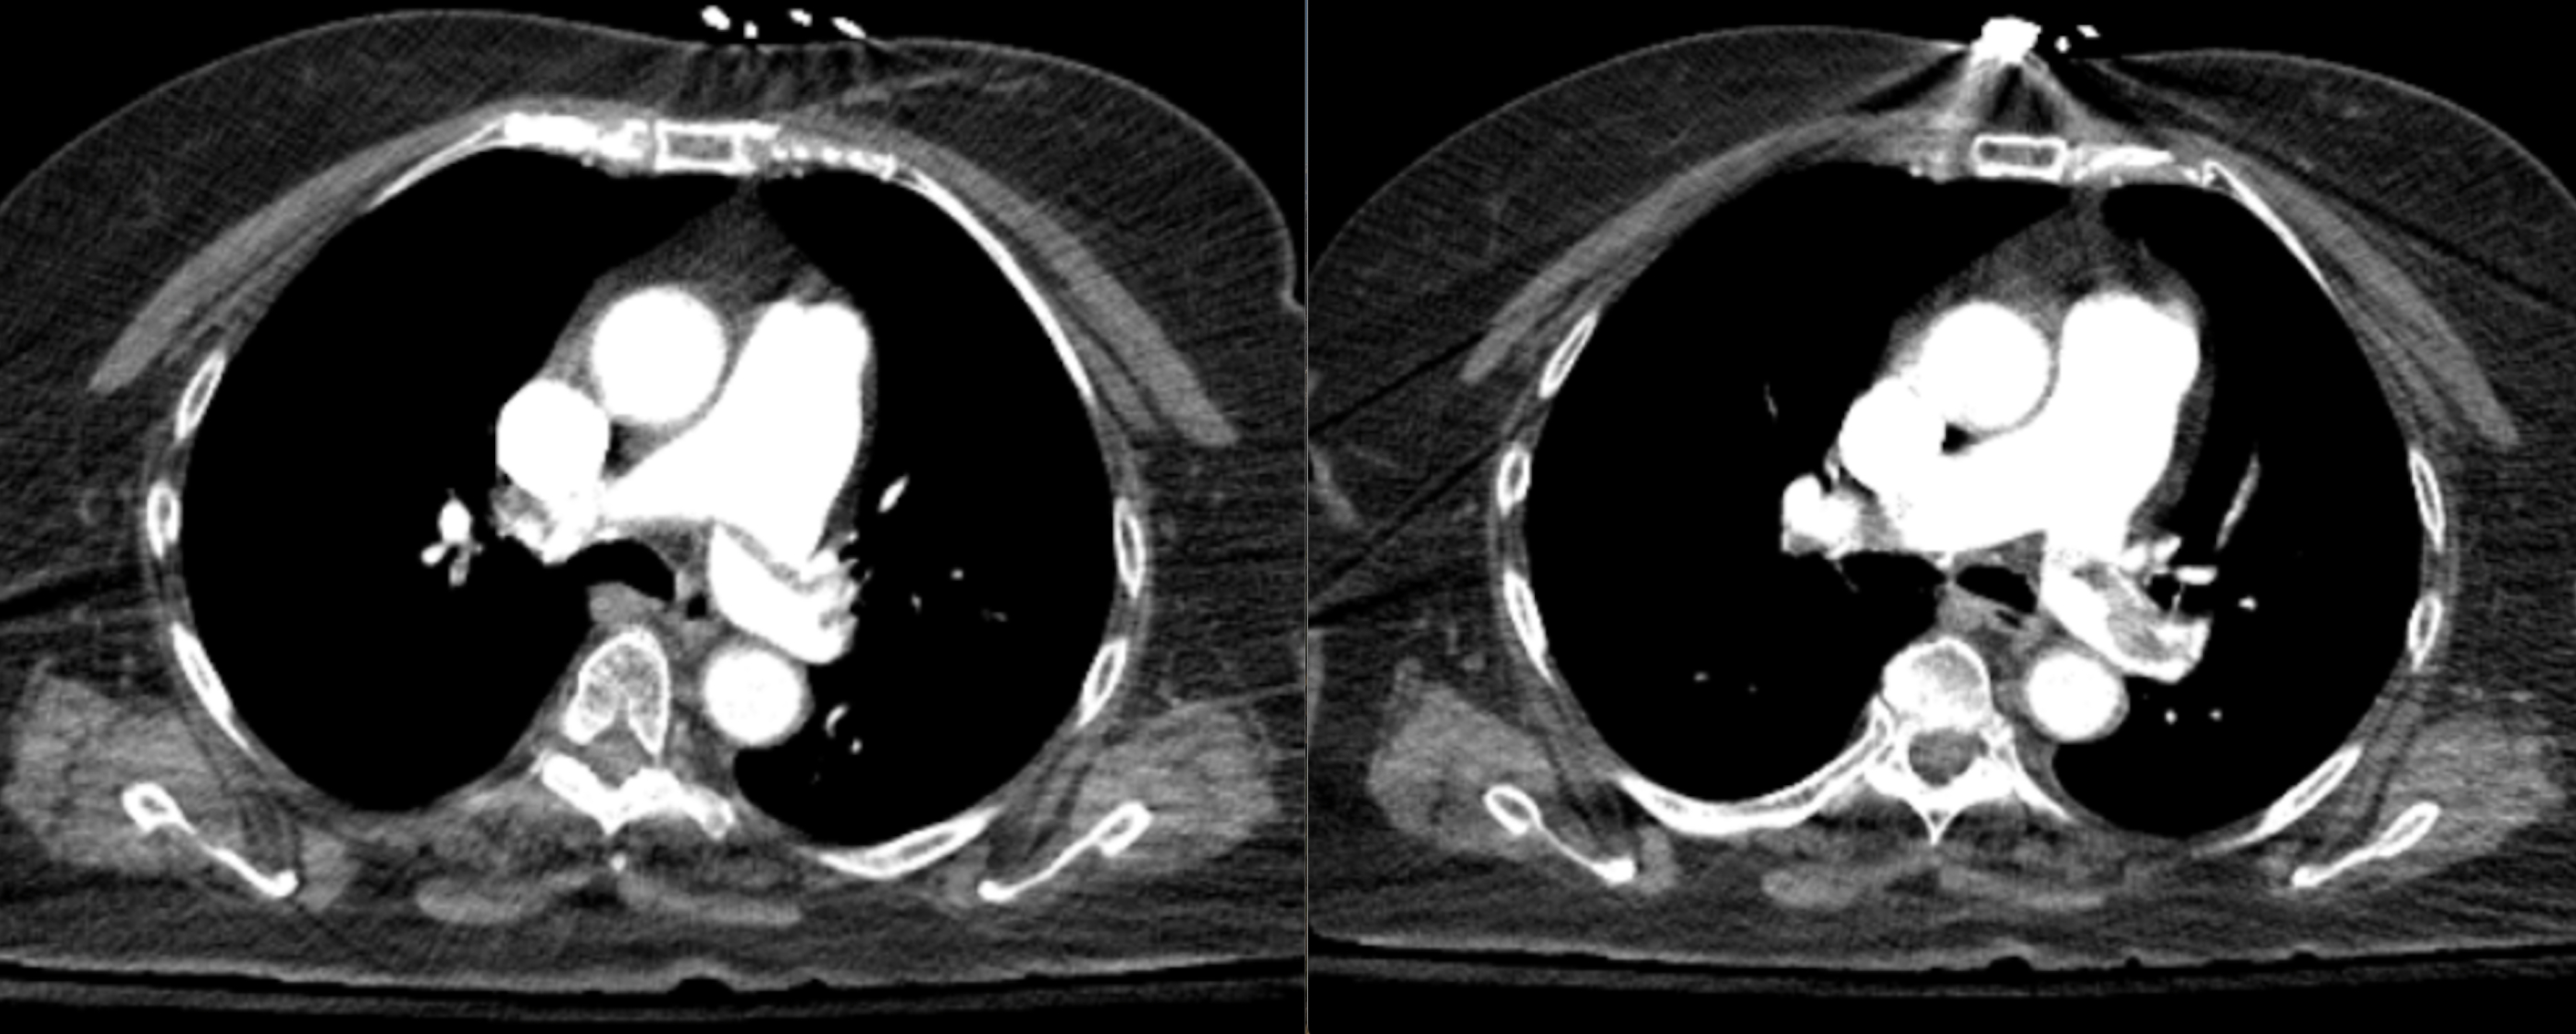

An ECG demonstrated sinus tachycardia with S1Q3T3 pattern, incomplete right bundle branch block (RBBB), inverted T wave in V1 and V3. Her Daniel Score was calculated at 9, indicating a high risk for hemodynamic instability. Troponin was 0.10 and BNP 8030. PE was suspected and a CTA confirmed a large saddle PE involving both main pulmonary arteries, with signs of RV strain, including RV dilation and contrast reflux into the IVC.